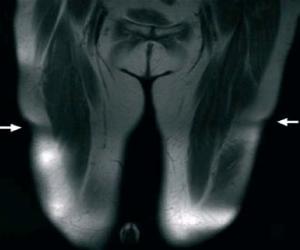

• Atrofia local del tejido subcutáneo sin afectación muscular.

• Lesión semicircular simétrica.

• Aparición en ambas piernas.